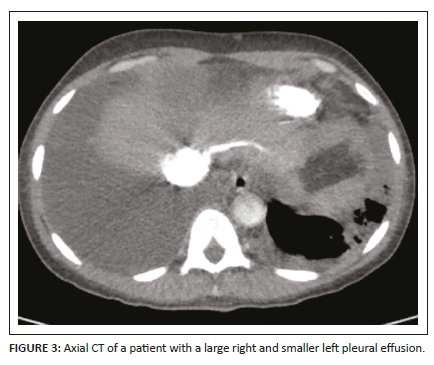

A complete list of the incidental findings on CTPA is summarised in Table 3 and the pulmonary findings in PE-negative cases are illustrated in Figure 2. The most common parenchymal findings in PE-negative cases were as follows: solid pulmonary nodules (52.5%), non-wedge-shaped consolidation (45%) (Figure 2a, b, c), emphysematous changes (17.5%) (Figure 2d) and lung cavities (10%) (Figure 2e, 2f). Pleural effusion was also found in 17% of PE-negative studies (Figure 3). One of the patients in the study had a pneumothorax (Figure 4). The most common incidental cardiac finding was cardiomegaly (52.5%). Various examples of extra-pulmonary incidental findings are demonstrated in Figure 5, including a case of extensive pneumobilia (Figure 5b) and a patient found to have multiple rib fractures (Figure 5c). The most common other intra-thoracic finding in PE-negative cases was enlarged mediastinal or hilar lymph nodes without significant mass effect (52.5%), whilst 7.5% had reported an oesophageal abnormality (Figure 5a); the most common extra-thoracic finding was hiatus hernia (7.5%).

Pleural effusion was present in 57% of the PE-positive cases in this study. This is higher than the 45% in the study on HIV-infected patients by Ramlakhan et al.11, as well as higher than the 25.8% in the study by Sharma et al.14 which did not include patients' HIV status. The most common parenchymal findings in our PE-positive group were pulmonary infarcts and mosaic attenuation (17.5% each), which is comparable with other studies carried out on both HIV-infected and -negative populations.7,11,14 These findings are traditionally thought to be due to PE. This study demonstrated an increased RV:LV ratio in nine of the 14 PE-positive patients (22.5%). There are no available data in the literature on the frequency of this finding in an HIV-infected study population with PE to compare with.